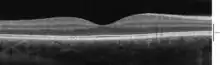

A number of different instruments are available for the diagnosis of diseases and disorders affecting the retina. Ophthalmoscopy and fundus photography have long been used to examine the retina. Recently, adaptive optics has been used to image individual rods and cones in the living human retina, and a company based in Scotland has engineered technology that allows physicians to observe the complete retina without any discomfort to patients.[62]

The electroretinogram is used to non-invasively measure the retina's electrical activity, which is affected by certain diseases. A relatively new technology, now becoming widely available, is optical coherence tomography (OCT). This non-invasive technique allows one to obtain a 3D volumetric or high resolution cross-sectional tomogram of the fine structures of the retina, with histologic quality. Retinal vessel analysis is a non-invasive method to examine the small arteries and veins in the retina which allows to draw conclusions about the morphology and the function of small vessels elsewhere in the human body. It has been established as a predictor of cardiovascular disease[63] and seems to have, according to a study published in 2019, potential in the early detection of Alzheimer's disease.[64]